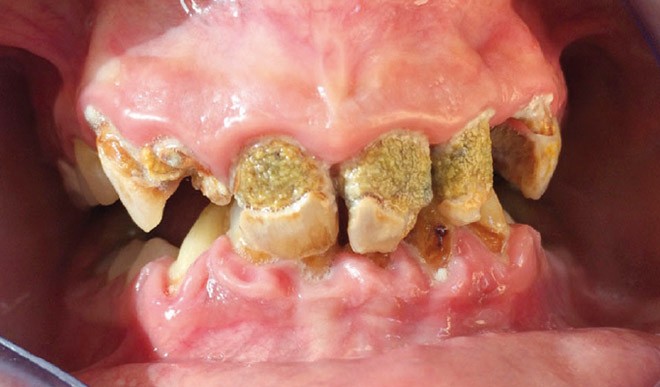

Les spécificités de la santé bucco-dentaire des patients à besoins spécifiques concernent notamment les déficits de l’hygiène buccale, les pathologies oro-faciales, les désordres esthétiques et fonctionnels et une plus grande proportion de pathologies parodontales [5, 6] (fig. 1).

Brown et al [6] ont relevé une prévalence de parodontites de 81 % chez les patients à besoins spécifiques, pour près de 93 % chez les plus de 60 ans et 56 % chez les 20-39 ans. Ils ont également noté une fréquence plus importante de caries et de pertes dentaires. Les difficultés de communication et les inconvénients liés aux différentes situations rencontrées font qu’une prise en charge au fauteuil (soins parodontaux, conservateurs puis restauration prothétique) demeure souvent difficile à mener à bien. Mais l’évolution dans les techniques de sédation, de CFAO, d’implantologie, de collage, est autant d’éléments qui optimisent le temps passé au fauteuil tout en garantissant une qualité de soins à la fois esthétique, fonctionnelle et pérenne à ces patients, même dans des situations « extrêmes » [1].